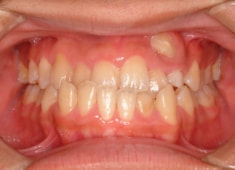

治療後(2年1ヶ月後)

反対咬合の治療は、FX(フェイシャルアキシス)が開きやすいのですが、治療後も良好な値を保つことができました。FXがあまり開きすぎると、咬合力が落ちてしまいます。

下顎の右側への偏位は解消されました。

特に左側の咬合時の顎関節の位置に改善が認められます。